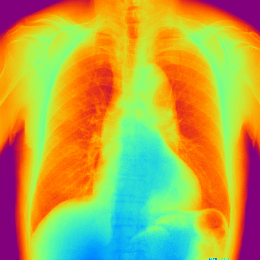

- 擬似カラー表示

擬似カラー表示